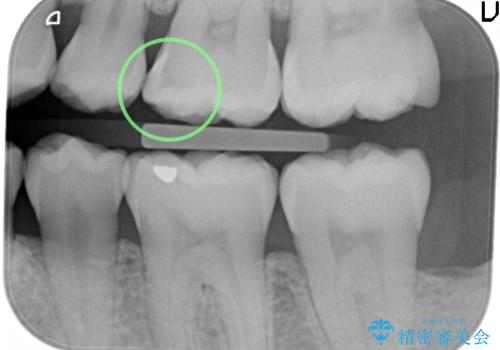

治療前の写真では虫歯はわかりにくいですが、レントゲンではっきり見えます。

虫歯は外の入り口は小さいままで、中で広がっていることが多いため、要注意です。

口の中を目で見てわかるレベルの虫歯ですと、進行してしまっています。

虫歯はレントゲンを取らないと、発見できません。

歯科検診はあくまで余程の状態のスクリーニングですので、きちんとレントゲンを定期的にとって、早期に治療することが重要です。